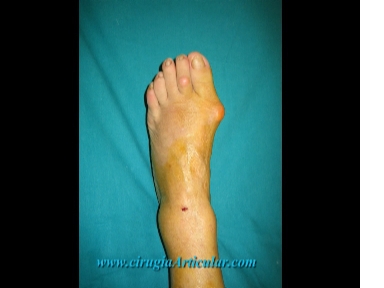

Foto 1

Esta cirugía se realiza con anestesia local. En esta fotografía se puede ver el pie con el juanete y los puntos de punción en el tobillo mediante los que se introduce el anestésico local.